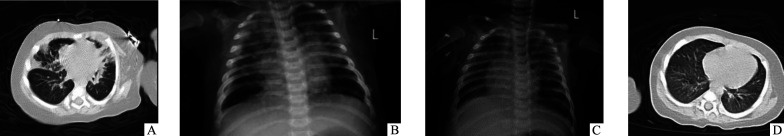

Pneumocystis jirovecii pneumonia (PJP) is an opportunistic pulmonary infection that commonly occurs in immunocompromised children. We report a case of infantile leukemia complicated by PJP and review the relevant literature. A summary and analysis of 10 infantile leukemia patients with PJP infection (9 cases reported in the literature and 1 case from our center) showed that PJP mostly occurred in the early stages of chemotherapy (80%, 8/10). The main clinical manifestations were dyspnea (100%, 10/10) and hypoxemia (50%, 5/10), while pulmonary imaging findings lacked specificity. In most cases (50%, 5/10), diagnosis was established by identifying pathogens in bronchoalveolar lavage fluid under microscopy. In our case, diagnosis was confirmed using targeted next-generation sequencing (tNGS) of bronchoalveolar lavage fluid. Treatment with intravenous sulfamethoxazole complex was administered in 8 patients, all of whom eventually recovered. PJP may occur in the early stages of chemotherapy for infantile leukemia, thus early prevention is necessary. tNGS facilitates early diagnosis of PJP, and sulfamethoxazole complex remains an effective therapeutic option.